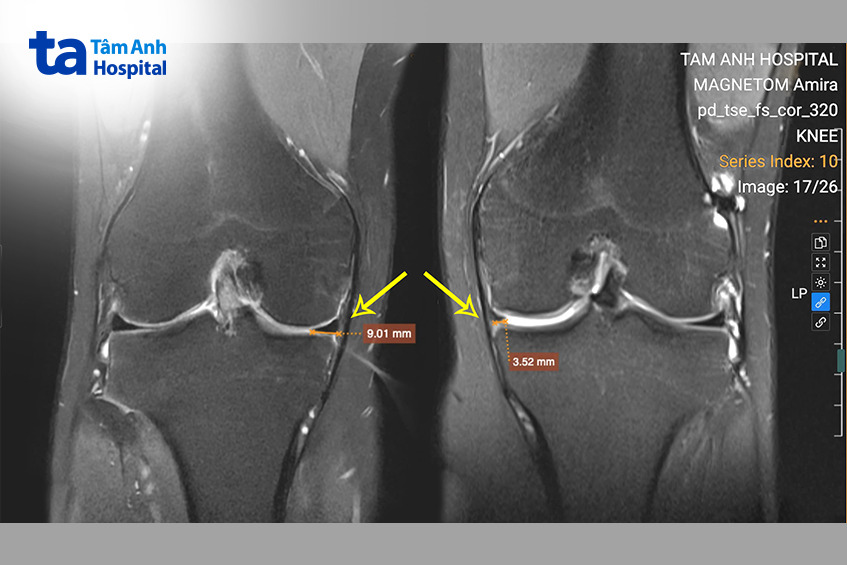

ThS.BS Nguyễn Quang Tôn Quyền, Phó khoa Chấn thương Chỉnh hình cho biết qua phim chụp cộng hưởng từ MRI, dây chằng chéo trước của Quang được tái tạo chắc chắn, nhưng sụn chêm trong đã bị cắt bỏ toàn bộ dẫn đến bệnh nhân vẫn có cảm giác lỏng gối.